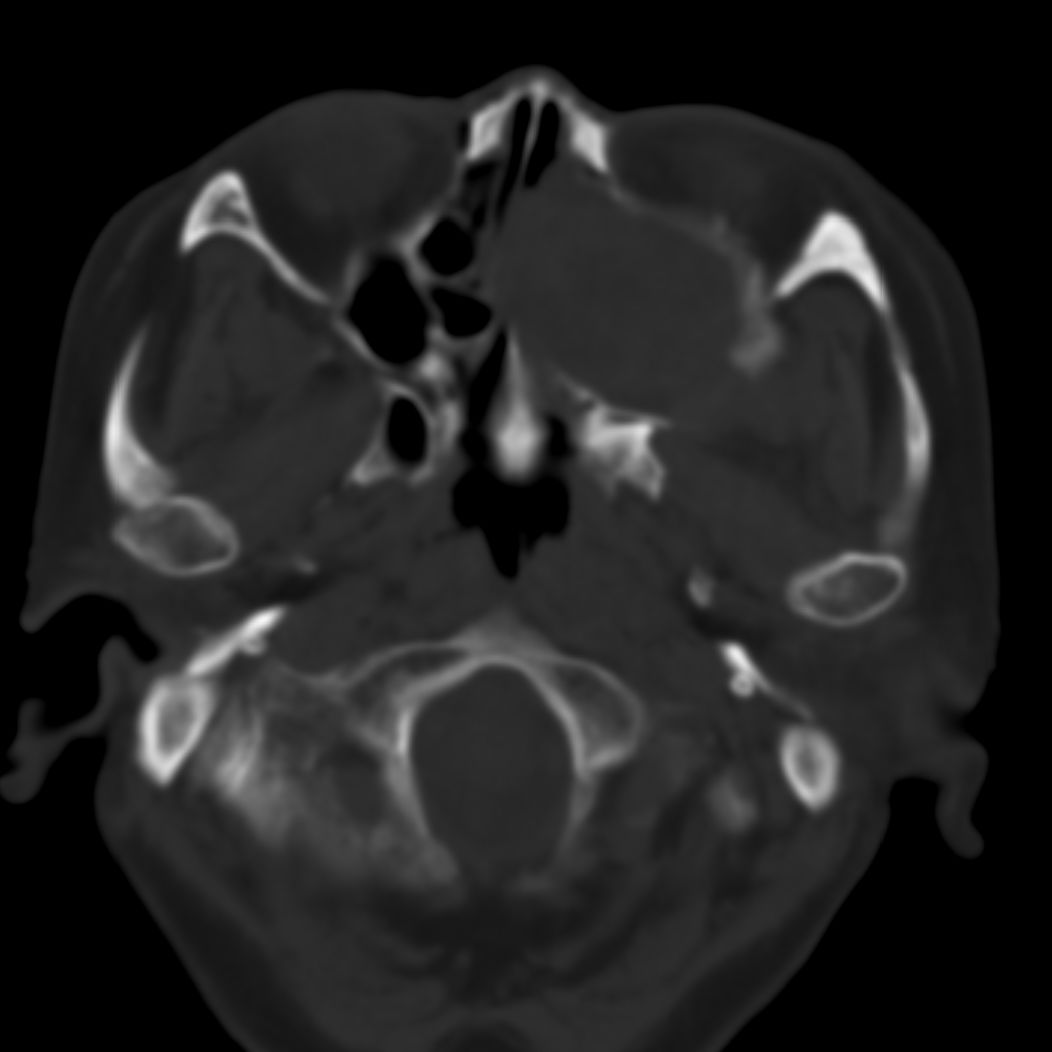

女,69岁。鼻出血2月多。(会诊病史就这样简单)鼻副窦ct检查如下:

左侧鼻腔及上颌窦见软组织块影,左侧上颌窦腔扩大,骨质吸收,右侧上颌窦见半圆形软组织密度影,鼻中隔向右侧弯曲,左侧鼻和鼻窦内翻型乳头状瘤可能性大,建议增强。

左侧上颌窦及鼻腔内见软组织密度影,其内密度不均匀,见斑片状高密度影,右侧上颌窦腔明显扩大,窦壁吸收变薄,鼻中隔右偏,右侧上颌窦见一半圆形软组织密度影,边界清楚,其内密度均匀。诊断,1、左侧鼻腔及上颌窦内翻乳头状瘤可能性大,上颌窦癌,息肉及霉菌性上颌窦炎待除外。2、右侧上颌窦粘膜下囊肿。

1)考虑左侧上颌窦内翻乳突状瘤突入左侧鼻腔。2)副鼻窦炎,右侧上颌窦黏膜下囊肿。

病理:霉菌性左侧上颌窦炎伴左侧上颌窦纤维组织增生。

窦腔密度不均匀增高,无明显钙化征象,后外侧及内侧窦壁膨胀明显,局部破坏消失,筛窦受累及,但双侧对比发现左侧窦壁骨质有硬化增白现象,这可能是支持左侧霉菌性上颌窦炎的主要依据点。